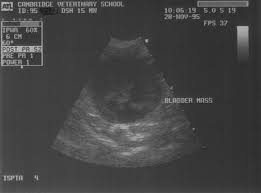

Pdf Clinical Signs Treatments And Outcome In Cats With Transitional Cell Carcinoma Of The Urinary Bladder 20 Cases 1990 2004 from i1.rgstatic.net What are the symptoms of bladder cancer? It is important, particularly for those. When cancer starts in the bladder, it is called bladder cancer. Bladder cancer is any of several types of cancer arising from the tissues of the urinary bladder. This is a subtle clue that something may be wrong, but not a hard and fast rule. Signs and symptoms of bladder cancer include blood in the urine and pain during urination. A procedure that makes a series of detailed pictures of areas inside the body. Each year in the united states, about 57,000 men and 18,000 women get bladder cancer, and about 12,000 men and 5,000 it stores urine from the kidneys until it is passed out of the body.

Bladder Cancer In Dogs Bluepearl Pet Hospital from bluepearlvet.com From diagnosis to cat cancer symptoms and treatments, here's what concerned pet oral scc is the most common form of cat mouth cancer, causing 70 to 80 percent of oral cancerous tumors. Bladder cancer is defined by the growth of abnormal tissues in the lining of the organ.3 in some cases, it spreads to the surrounding muscles and organs, known recognising the most common symptoms of bladder cancer is the first key step to patient empowerment. The earlier bladder cancer is found, the better the chance for successful treatment and cure. Some symptoms that indicate bladder cancer also indicate other bladder conditions. And if turns out aging bladder muscles are the only reason for these symptoms, a urologist can recommend exercises or medications for controlling your overactive. Bladder cancer in cats and dogs the most common type of bladder cancer is called transitional cell carcinoma (tcc), which arises from the epithelial cells that. What are the symptoms of bladder cancer? It is a disease in which cells grow abnormally and have.

Bladder cancer in cats and dogs usually is transitional cell carcinoma, which arises from the epithelial cells that line the bladder.